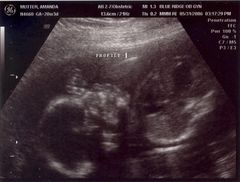

August 8, 2006: Another Ultrasound

Little did my parents know I'd be making my entrance in less than a month. The OB didn't suspect either :-)

My face is recognizable already.